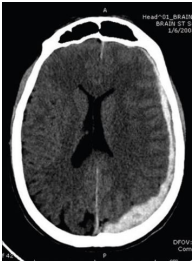

Paciente vítima de traumatismo cranioencefálico, após avaliação primária e secundária, realiza um exame de imagem. No que diz respeito ao caso hipotético e à interpretação do exame de imagem, assinale a alternativa que apresenta a hipótese diagnóstica correta.